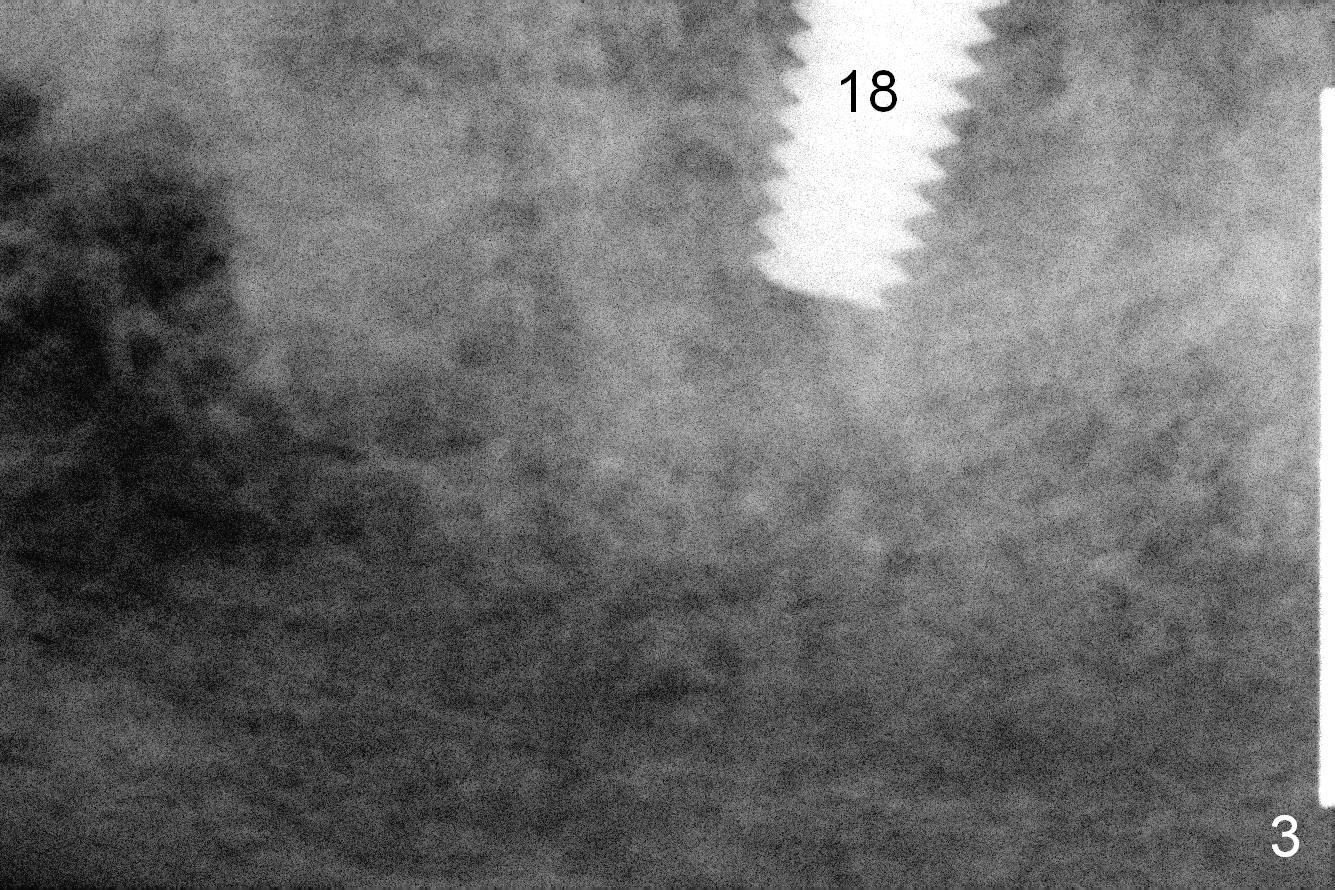

The sites of osteotomies at #18 and 20 are decided by the surgical stent (Fig.1). A 4x14 mm implant is placed at the site of #20 (Fig.2), and a 5x14 mm one at #18 (Fig.3) with primary stability. When 3 mm long abutments are placed for an immediate provisional (Fig.4 A), there is no or limited clearance with the opposing dentition (Fig.5). In spite of the fact that the implants are placed deeper, the abutments and the opposing supraerupted teeth #13 and 15 (Fig.5 arrows) have to be reduced. Finally the abutment at #18 has to be removed. No provisional is fabricated. Periodontal dressing is applied around the abutment at #20 and the adjacent teeth. It appears that the tissue-level implant is not suitable for the 2nd molar with limited vertical clearance.

There is bone loss at #18 3.5 months postop with mild purulent discharge from the gingival sulcus (1 month post healing cuff placement, Fig.6). After heavy abutment and the tooth #15 reduction, the provisional FPD has to be made to increase vertical height.